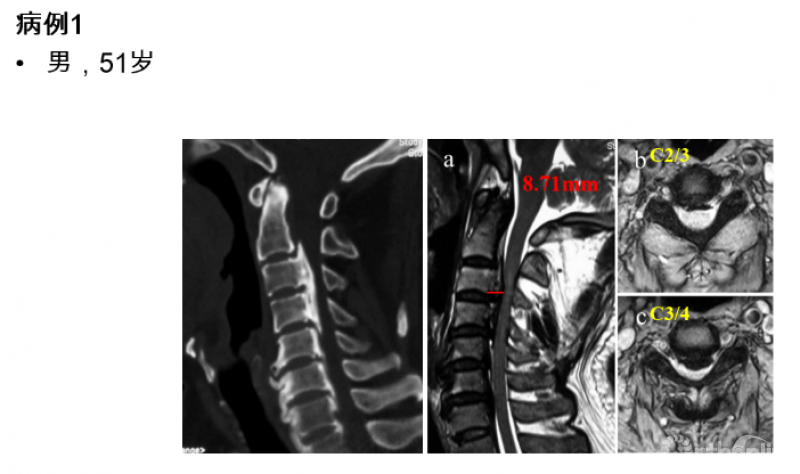

图1

从该患者的影像资料可以发现以下特点:致压物主要是来自于脊髓前方的后纵韧带骨化块,造成脊髓腹侧受压。在颈2/3间隙及以上水平,并未造成脊髓明显压迫,但在C3/4间隙水平椎管侵占率陡然增大,是脊髓受压最严重的节段。在这种情况下,颈后路纵向减压范围应该是C3-7、C2-7或者C1-7?

实际上,类似于病例1的情况并不少见,尤其多见于后纵韧带骨化症的患者,暂且不对例1的治疗方案做出决定,我们来看另一例给我们启示的病例:

图2

对于该例患者,C2/3间隙水平有轻度脊髓压迫,脊髓受压最重的节段仍然在C3/4水平。我们进行了再次手术,并向头侧扩大减压范围至C2,术后不仅C2/3水平的轻微压迫得到解除,C3/4水平脊髓压迫也明显去除了(图3),神经功能改善。

这个病例给我们的启示是:扩大减压范围至C2,有助于提高C3/4水平脊髓减压的效果。然而,显然并不是所有患者都需要扩大减压,那么需要回答的问题是:C3/4水平的脊髓前方致压物多大,需要扩大减压范围至C2?

图3 术后核磁显示脊髓减压充分

我们对57例患者的资料进行回顾,按减压节段分为C3-7组(n=32)和C2-7组(n=25)。测量并比较两组患者术后核磁上C2/3至C7/T1各节段脊髓前方至椎体后缘的距离(图4,在本研究中命名为脊髓前间隙,Anterior cord space, ACS),以了解不同的减压范围下减压效果的差异,以及将减压范围扩大至C2能带来的脊髓减压效果的获益究竟有多大。从而回答上述临床问题。

图4

本研究的结果提示,扩大减压范围至C2后,不仅使C2/3水平ACS增加,其相邻的C3/4水平ACS亦有明显增加,提高了C3/4水平避让前方压迫的能力(图5)。

图5

从数值上进行分析可以发现:C3-7组C3/4水平ACS均值6.60mm(95%CI:6.10~7.11),当该水平致压物中矢径>6.10mm时,C3-7减压即可能在C3/4水平残留压迫,当C3/4水平致压物中矢径>7.11mm时,C3-7减压则几乎不能充分解除压迫;如果扩大减压范围至C2,C3/4水平的ACS平均可达8.74mm(95%CI:8.10~9.38),最大可避让中矢径为9.38mm的前方致压物(图6)。

图6

此外,C4-5及以下节段未受C2减压的影响,提示当目标节段及其相邻节段的椎管充分扩大后,该目标节段即获得最大减压效应,而不会受到远隔节段是否减压的影响,亦即颈椎后路减压的效应主要受局部因素(局部硬膜囊膨起及局部曲度)的影响,这与系列一的研究结果是一致的。

最后,我们回到病例一,利用上述研究结果指导临床决策:C3/4水平致压物中矢径8.71mm>7.1mm,所以C3-7减压势必残留压迫,应选择C2-7减压,术后获得了9.34mm的ACS,充分解除了脊髓压迫(图7)。

图7